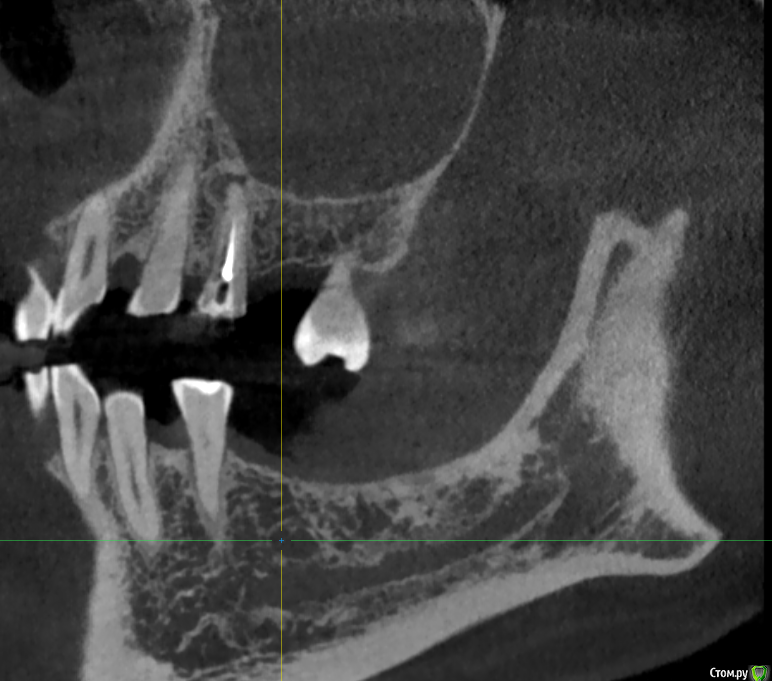

Женька Опубликовано 9 июня, 2020 Поделиться Опубликовано 9 июня, 2020 Тоже спрошу, чтобы не плодить темы.Пришла вот такая пациентка, удаление 28 февраля 2020. Думаю, что ничего страшного и можно ставить не взирая на образование, по крайней мере, мне видится, что это не апексы... тень думаю, потому, что лунка всё еще в стадии заживленияЧто скажете, коллеги? Ссылка на комментарий

Irouil Опубликовано 9 июня, 2020 Поделиться Опубликовано 9 июня, 2020 Как минимум один кусочек чего-то белого на последнем срезе есть Можно ещё прицелку посмотреть. А что с анамнезом? Ссылка на комментарий

Женька Опубликовано 9 июня, 2020 Поделиться Опубликовано 9 июня, 2020 Как минимум один кусочек чего-то белого на последнем срезе есть Можно ещё прицелку посмотреть. А что с анамнезом?В анамнезе у бабушки Cr желудка.Прицела к сожалению нету пломбировочный материал? мне кажется он В остальном считает себя здоровой, по врачам не бегает, на учётах не состоит. Во время удаления (удалял не я) делали прицелы после, и тоже увидели это образование (со слов пациентки). Ссылка на комментарий

Fin Опубликовано 9 июня, 2020 Автор Поделиться Опубликовано 9 июня, 2020 В анамнезе у бабушки Cr желудка.Прицела к сожалению нету пломбировочный материал? мне кажется он В остальном считает себя здоровой, по врачам не бегает, на учётах не состоит. Во время удаления (удалял не я) делали прицелы после, и тоже увидели это образование (со слов пациентки).Удаление 28 было, а когда сделано КТ?. По мне да, лунка в стадии заживления, если вы про дистальное образование то это одонтома, а вот на верхушке гребня что то есть. Думаю что ничего страшного,сделаете прицельный снимок перед имплантацией и если что во время операции уберете. Ссылка на комментарий

red_butler Опубликовано 9 июня, 2020 Поделиться Опубликовано 9 июня, 2020 Что скажете, коллеги? я бы удалил и возможно на гистологию отправил 2 Ссылка на комментарий

red_butler Опубликовано 9 июня, 2020 Поделиться Опубликовано 9 июня, 2020 Кт от 8 июня. Из-за анамнеза родословной?Нет, новообразование имеет оболочку, не хотелось бы удалять имея там имплант 1 Ссылка на комментарий

Женька Опубликовано 9 июня, 2020 Поделиться Опубликовано 9 июня, 2020 Записал срезы Кт, вижу что-то похожее на корень с ярким материалом в области края гребня. И образование, по плотности как кортика. + лунки заживающие. Ссылка на комментарий

red_butler Опубликовано 9 июня, 2020 Поделиться Опубликовано 9 июня, 2020 https://youtu.be/1pW5wBBAbls Записал срезы Кт, вижу что-то похожее на корень с ярким материалом в области края гребня. И образование, по плотности как кортика. + лунки заживающие.Похоже на корень. А есть снимки до удаления? И настораживает, зачем коллеги делали rg после удаления.., Ссылка на комментарий

Женька Опубликовано 9 июня, 2020 Поделиться Опубликовано 9 июня, 2020 Похоже на корень. На верхушке гребня с ярким рентгеноконтрастным материалом? или где-то в другом месте? А есть снимки до удаления? Была вроде ОПТГ, попробую вытянуть у пациентки.И настораживает, зачем коллеги делали rg после удаления..,Именно из-за этого плотного образования. Ссылка на комментарий

Irouil Опубликовано 10 июня, 2020 Поделиться Опубликовано 10 июня, 2020 я бы удалил и возможно на гистологию отправилТут мне кажется верное решение Похоже на какую-то цементому не удалённую, но все же Ссылка на комментарий

Irouil Опубликовано 10 июня, 2020 Поделиться Опубликовано 10 июня, 2020 Возможно меня неправильно поняли) у бабушки пациентки был Cr в анамнезе...Или разницы нет и не стоит имплантировать пока не уберу образование?Но тогда другой вопрос, как оптимальнее его вытащить? или не важно и всё равно придется аугментировать и ждать?Про бабушку я понял. Но если эта штука осумкована (а на орто до тоже так кажется), то вокруг импланта пойдёт расти ее капсула, а не кость. По крайней мере есть такой риск. Ну а на гистологию всегда лучше сдать, чем не сдать Ссылка на комментарий